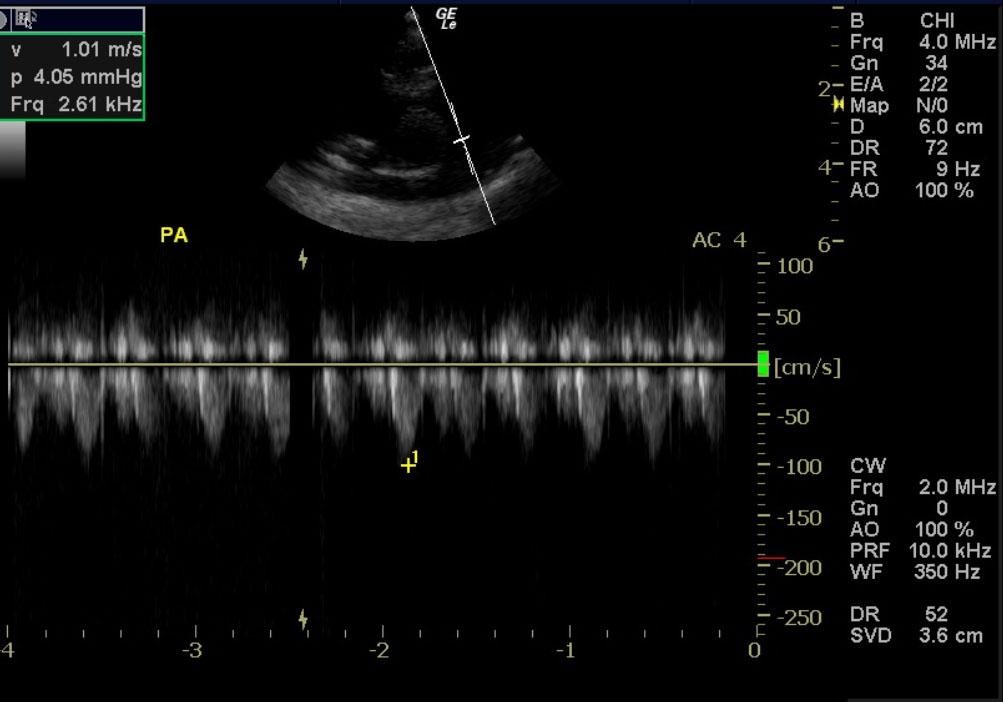

A one month old sheltie cross dog with a history of 5 of 7 littermates dying from parvovirus was presented for lethargy, and diarrhea. Parvovirus was identified in a littermate’s myocardium at necropsy.